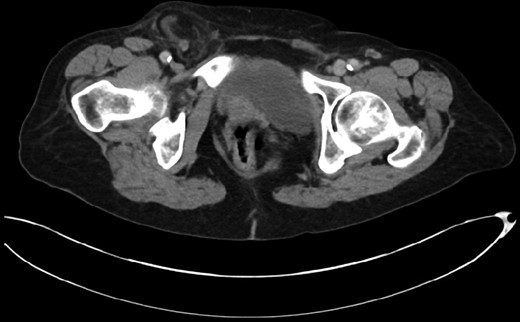

This 82-year-old lady presented with a sudden painful right sided groin swelling not previously noticed. She had no features of obstruction and was opening her bowels and not vomiting. Her medical background included left sided femoral hernia repair in 2005, coronary artery bypass graft and bilateral total knee replacements. On examination her abdomen was soft with the presence of a tender, irreducible swelling in the right groin, inferolateral to the pubic tubercle. She had good bowel sounds and there was stool present in the rectum on PR examination. A full set of blood tests demonstrated no abnormality. A CT abdomen and pelvis demonstrated an incarcerated right sided femoral hernia containing an 8 mm long inflamed appendix with a small amount of localized free fluid and inflammation indicative of De Garengeot’s hernia with underlying acute appendicitis (Fig. 1). The hernia sac diameter measured 2 mm on CT scan. She was taken to theatre for an open Lockwood repair of her femoral hernia and an appendicectomy. Following an initial Lockwood incision over the lump, dissection was performed down to the hernia sac also exposing the inguinal ligament (Fig. 2). The tightness of the femoral ring made mobilization of the appendix difficult. By partially incising the inguinal ligament superior to the femoral ring, the appendix was freed, and on inspection showed inflammation particularly towards the tip (Fig. 3). The caecum was then reduced and the inguinal ligament was repaired with non-absorbable suture. The femoral hernia was then repaired with a small funnel of ultrapro mesh. Appendicectomy was then performed in the usual fashion via the Lockwood incision leaving a slightly longer stump than usual (Fig. 4).

Vermiform appendix freed from hernial sac showing inflammation towards the tip.